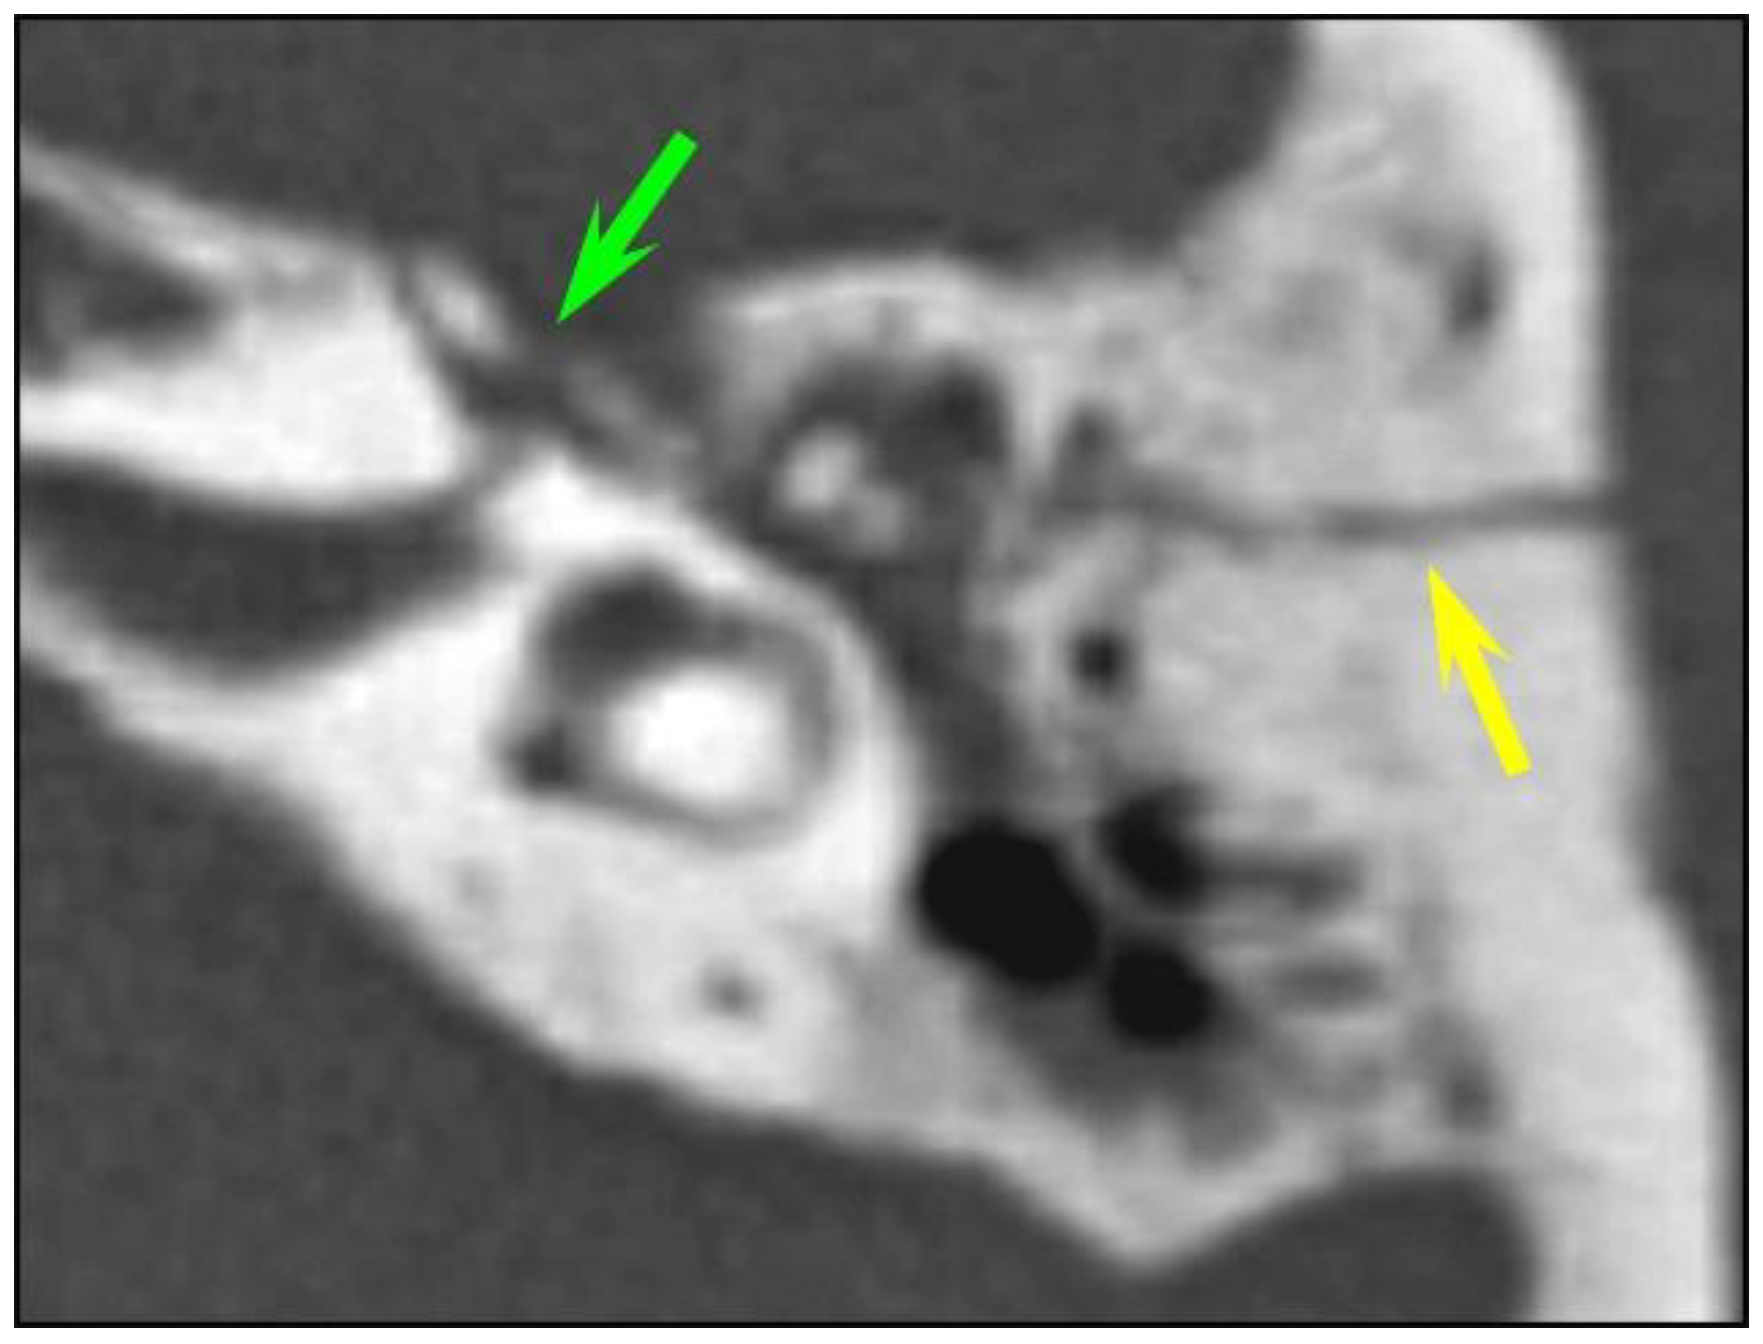

Figure 3. Ossicular chain dislocation. A polytrauma patient with otorrhagia. CT of the left temporal bone (axial plane). (a,b) Longitudinal fracture (yellow arrow); the malleus head (green arrow) is displaced and isolated from the incus body (pink arrow), corresponding to an incudo-malleolar luxation.

Eleven temporal bone fractures (11/126, 8.7%) showed involvement of the ossicular chain. The incudo-mallear joint was the most frequently injured joint (n = 6), displaying luxation or subluxation (Figure 3). Other injuries were complete incus dislocation (n = 3) and incudo-stapedial luxation (n = 2). Fractures of the tympanic cavity walls were much more common (67/126, 53.2%) than ossicular dislocations. Likewise, fractures of the external auditory canal–temporomandibular joint complex were more common than ossicular chain injuries (91/126, 72.2%).

In our study, ossicular chain injuries were slightly more common in children (13.7%) than in adults (7.7%), and the incudo-mallear joint was the most frequently injured joint in both groups, followed by incus dislocation and incudo-stapedial luxation. Similar results were seen in a case series by Meriot et al. which showed that incudo-mallear joint dislocation was the most common ossicular abnormality (59%), followed by incudo-stapedial joint dislocation (53%) and incus dislocation [17]. As pointed out by different authors, ossicular dislocation can be very subtle. Subluxation of the incus without obvious displacement and with only a minor increase in the space between the articulation surfaces of the incus and malleus can be easily missed on an initial CT scan obtained in an emergency situation. Likewise, the diagnosis of incudo-stapedial luxation can be easily missed unless dedicated 2D oblique reconstructions are obtained. The presence of hemotympanum further hampers ossicular evaluation, especially of the stapes superstructure due to the very small size of the two crura. In our study, most ossicular chain injuries (72.7%) were missed by the resident on call; however, they were detected at a retrospective CT evaluation by specialized head and neck radiologists. Patients with ossicular dislocation typically present with conductive hearing loss persisting several months or years after temporal bone trauma, and the reported delay between the initial injury and diagnosis followed by treatment is within a range of 5–6 years [18]. As post traumatic ossicular dislocation also occurs with head trauma without temporal bone fracture, ossicular disruption should be suspected in all patients with conductive hearing loss persisting after 2-months of the healing process [18]. In these patients, a high-resolution CT is recommended to facilitate diagnosis as the hemotympanum usually resolves 2 months after trauma. Fractures of the malleus, incus or stapes are exceedingly rare and tend to occur after digital manipulation of the external auditory canal or from torsional injuries. As expected, we did not detect any ossicular fractures in this series.